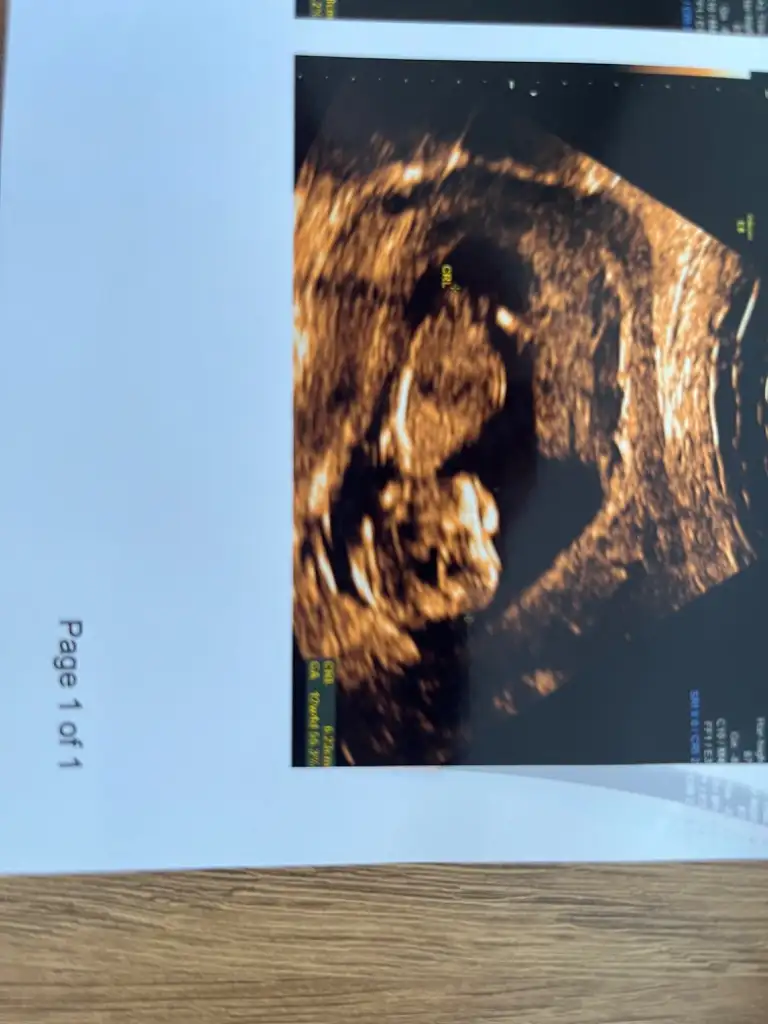

Banada bı yorum yapın bacılarım 12 haftalık görüntüsü